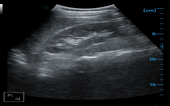

Kidney

Kidney